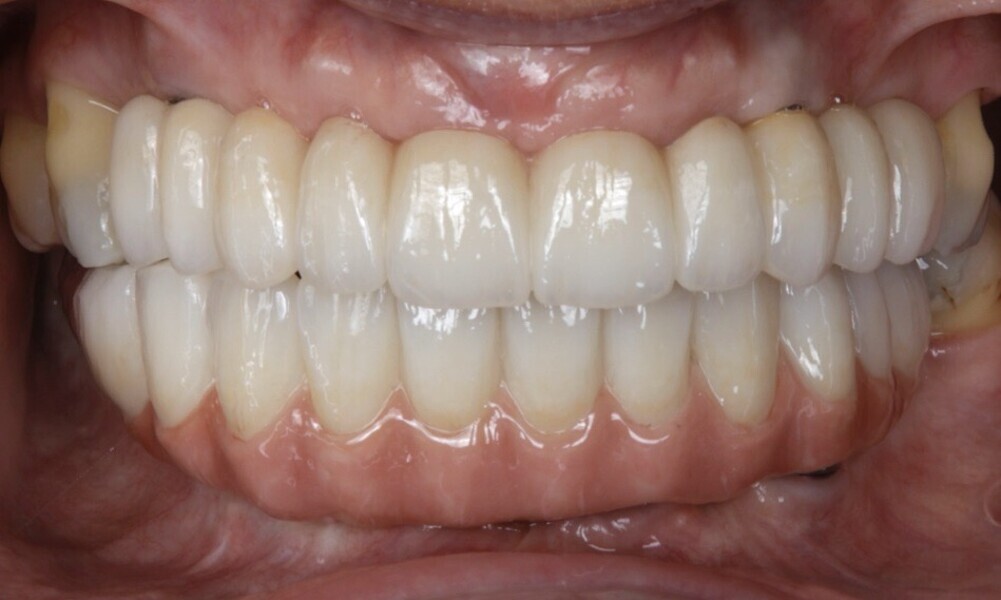

After a healing period of five months and successful osseointegration, the process for the definitive restorations was initiated. The chosen material was milled monolithic zirconia, and Variobase final abutments was used, placed on the screw-retained abutments to ensure excellent stability and retention of the definitive restorations (Figs. 69–75).

The soft tissue was in good condition, and the definitive restorations were placed (Figs. 76 & 77). After placing the definitive restorations, oral hygiene instructions were given to ensure proper care and prevent complications. Additionally, the occlusion was carefully checked and adjusted as needed (Figs. 78–83).

Figs. 78–82: The definitive restorations were placed, and occlusal adjustments were performed.

Treatment outcomes

Good results were achieved regarding both hard and soft tissue, as well as aesthetics. The patient shared the following testimonial: “I couldn’t be happier with my new smile! The process was so precise and seamless, and I felt involved every step of the way. The digital planning made it clear what to expect, and the results are beyond what I imagined—natural, beautiful and perfectly suited to me. Eating and smiling feel effortless again. It’s truly life-changing!”

Fig. 83: The definitive restorations were placed, and occlusal adjustments were performed.